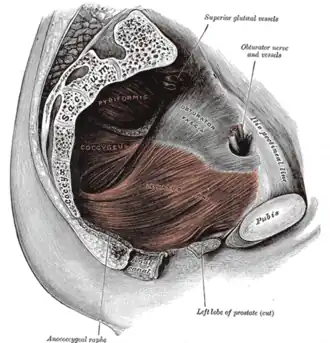

Colonne vertébrale. Releveur de l'anus.

Releveur de l'anus. branches postérieures des nerfs sacrés.

branches postérieures des nerfs sacrés. Coupe sagittale médiane du pelvis masculin.

Coupe sagittale médiane du pelvis masculin. Coupe sagittale médiane du pelvis féminin.